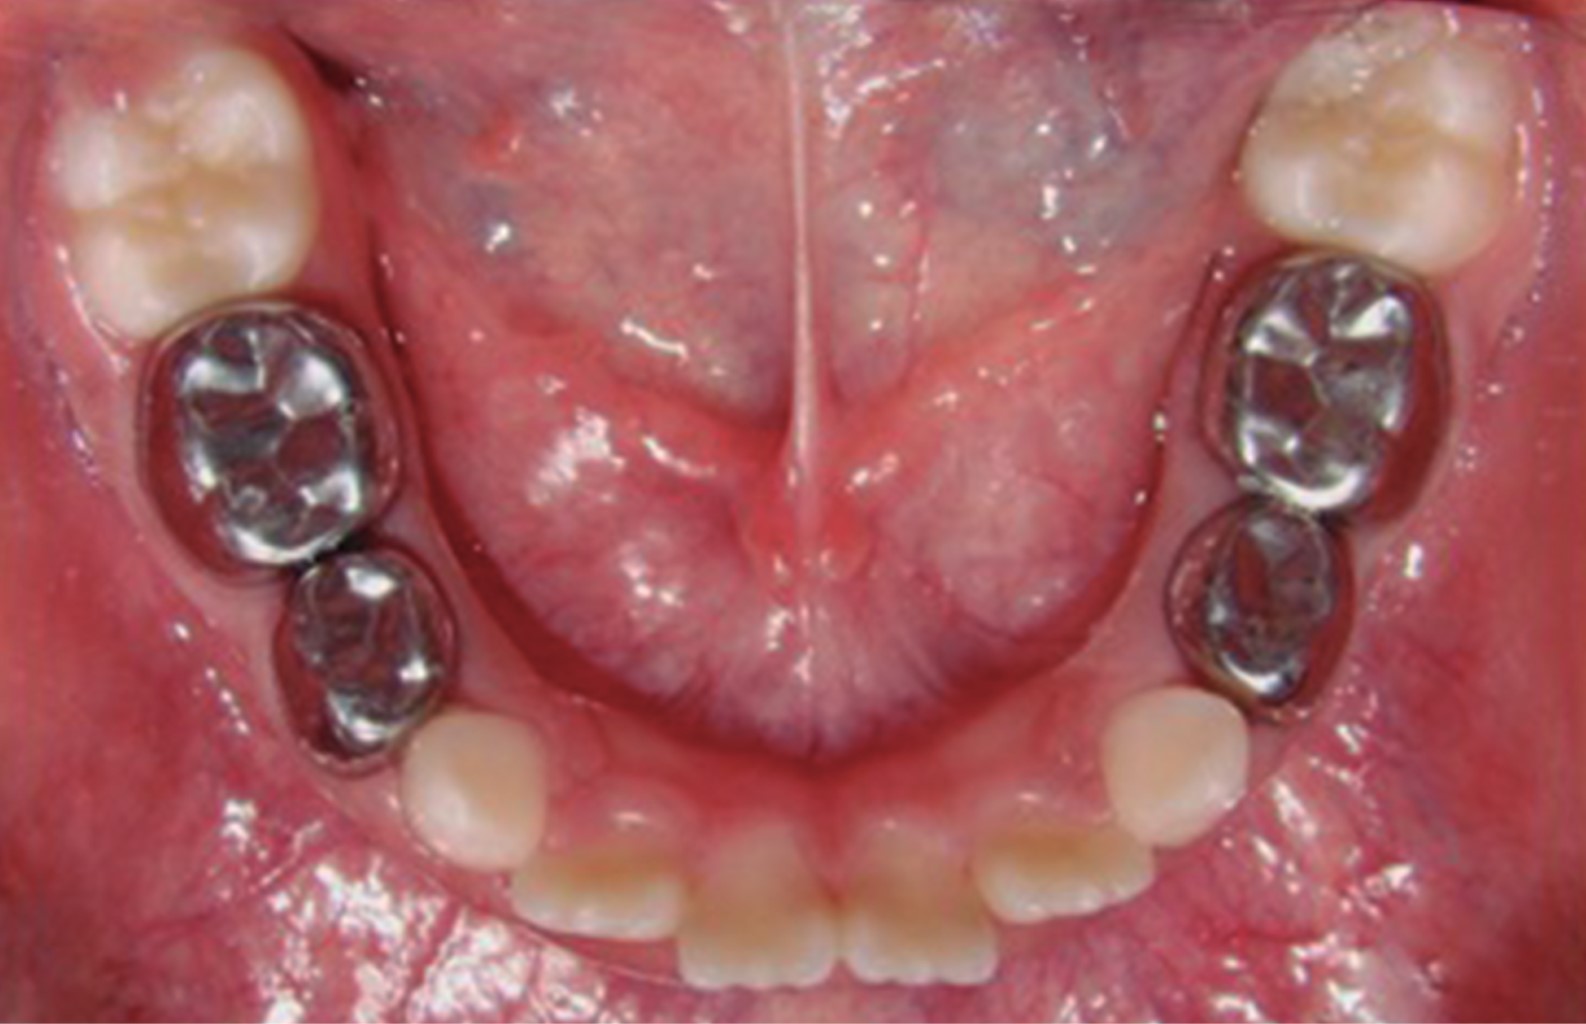

Figure 3